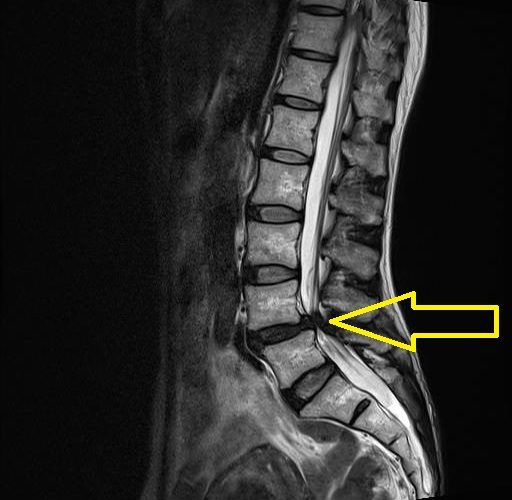

これを「特異的腰痛」と呼び、その代表例が腰部脊柱管狭窄症と腰椎椎間板ヘルニアです。

背骨は24個の椎骨が積み重なって構成されており、その中央に神経の通り道である脊柱管があります。

この中には脊髄や馬尾神経、靭帯などが通っています。

背骨にゆがみや変形が生じると、体はそれを支えようとして骨や靭帯を厚くします。

その結果、脊柱管が狭くなり、神経の圧迫や血流障害が起こり、痛みやしびれにつながります。

椎間板ヘルニアは、椎骨と椎骨の間にある椎間板が外に飛び出し、神経を刺激することで起こります。

椎間板は、中心部の「髄核」と、それを包む「線維輪」という組織で構成されています。

強い負担や繰り返されるストレスによって線維輪が傷つくと、髄核が外へ飛び出します。

この際に炎症物質が漏れ出し、神経に炎症を起こすことで痛みやしびれが生じます。